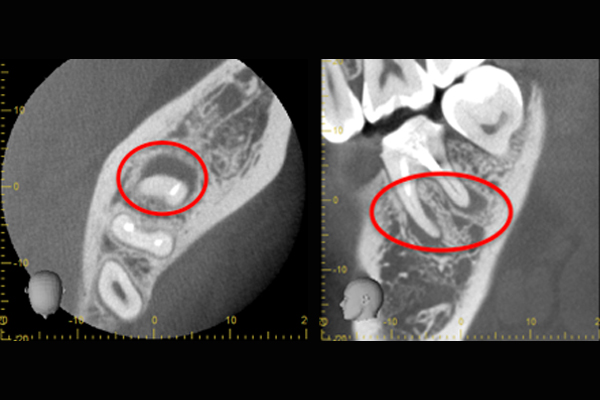

更に、拡大すると歯根破折に加え、器具の破折片も確認できる。

心臓の鼓動のように『ドク・ドク』と浸出液が出ているのが分かる。